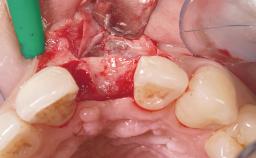

Immediate Flapless Placement of an Implant in a Maxillary Left Central Incisor Site

A 29-year-old female patient presented for treatment to replace the upper left central incisor tooth with an implant- supported restoration. The tooth had been intermittently symptomatic for the previous 12 months. The tooth had originally suffered trauma about 15 years previously. Several endodontic treatments had been performed, including an apicectomy procedure to retain the tooth. The patient was healthy and a non-smoker. She had reasonable expectations in regard to esthetic outcomes and the risk of marginal tissue recession following treatment. At medium smile, the gingival margins of the upper teeth were visible, with a display of 3 to 4 mm of the gingival margins. Gingival recession of tooth 21 and a discrepancy in the gingival levels between teeth 11 and 21 was observable during normal speech and smile.

| Soft Tissue Grafting | None |

| Soft Tissue Anatomy | Intact | Defective | |

| Soft Tissue Contour and Volume | Slightly compromised |